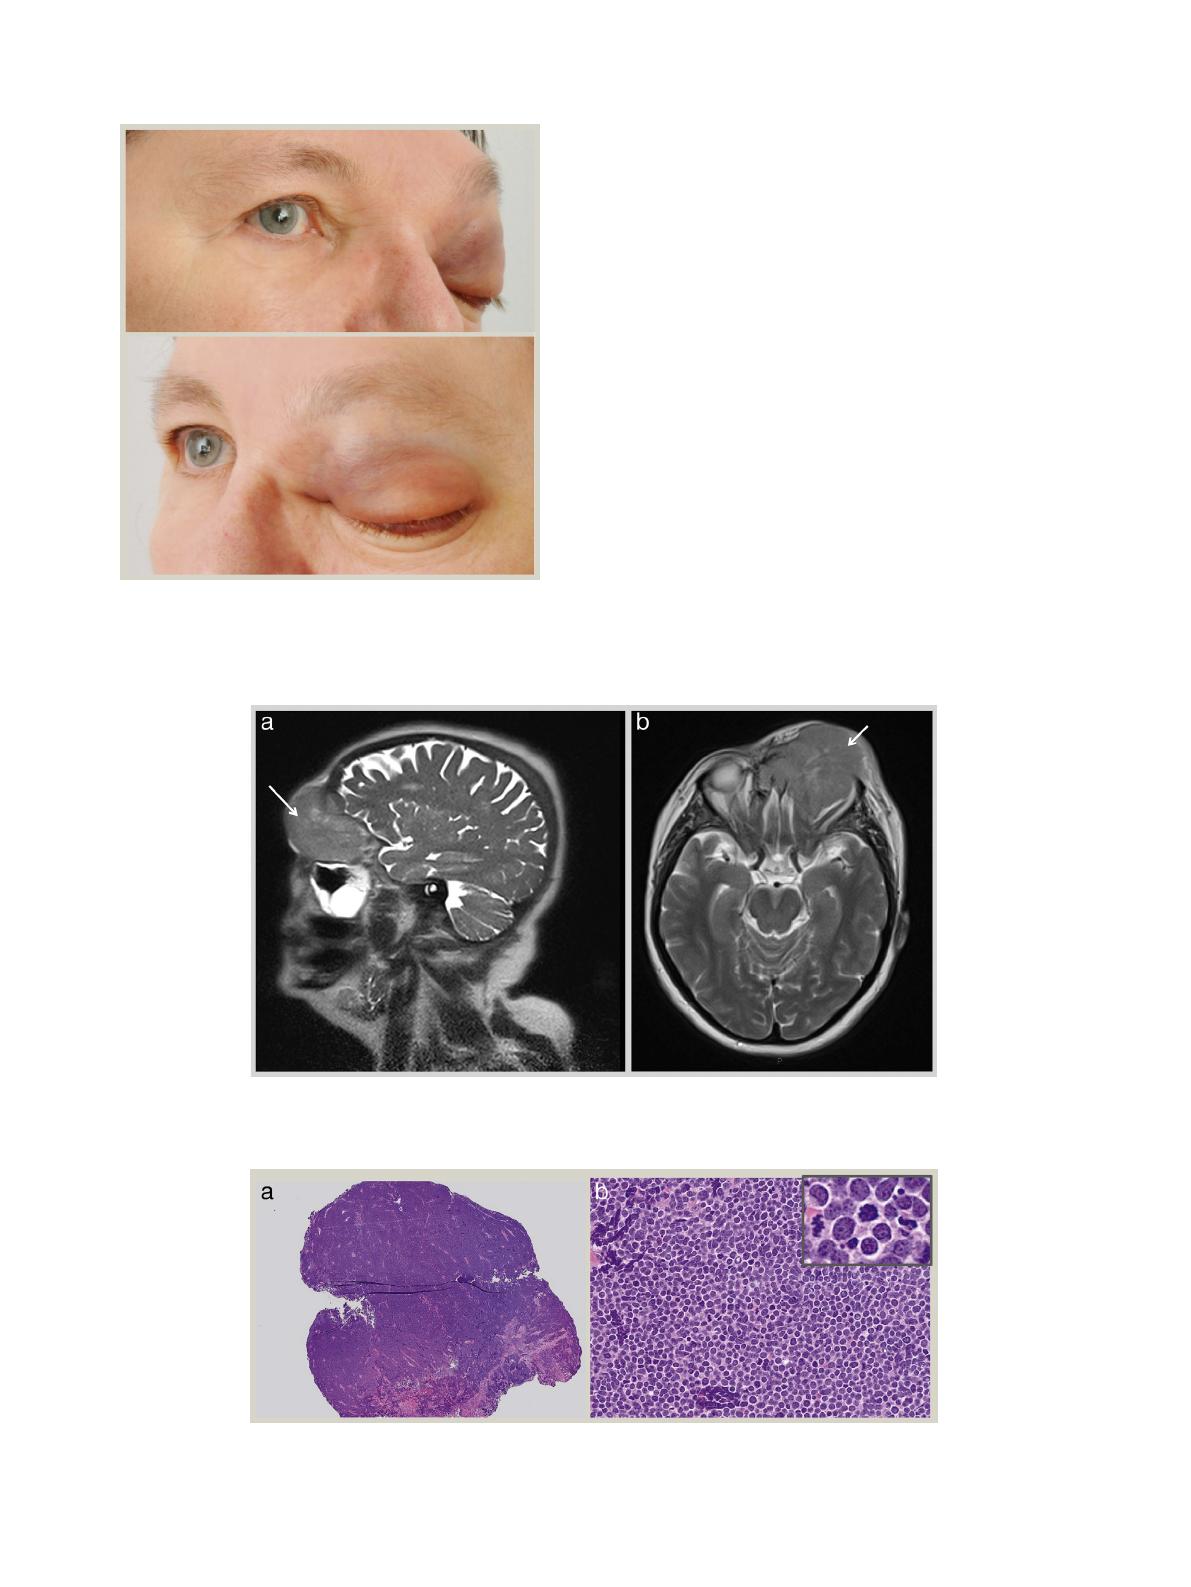

On examination, vision in the affected eye was hand move-

ments and in the right eye was 6/9 aided. There was a palpable

mass left peri-orbital mass, marked anterolateral proptosis

(Figure 1) and a fixed globe with no extraocular movements.

An MRI scan of the head and orbits with contrast (Figure 2)

showed a left orbital tumour (white arrows) measuring 7 5.4

6 cm displacing the globe anterolaterally and extending to the

paranasal sinuses, left nasal cavity with bifrontal extradural

extension.

Macroscopic examination showed a gelatinous pale mass

measuring 12 86 mm.

Histological examination revealed extensive infiltration of

lesional tissue with medium-sized cells with a high nuclear:cy-

toplasmic ratio, stippled chromatin and scant cytoplasm. There

were numerous mitoses and apoptotic bodies (Figure 3).